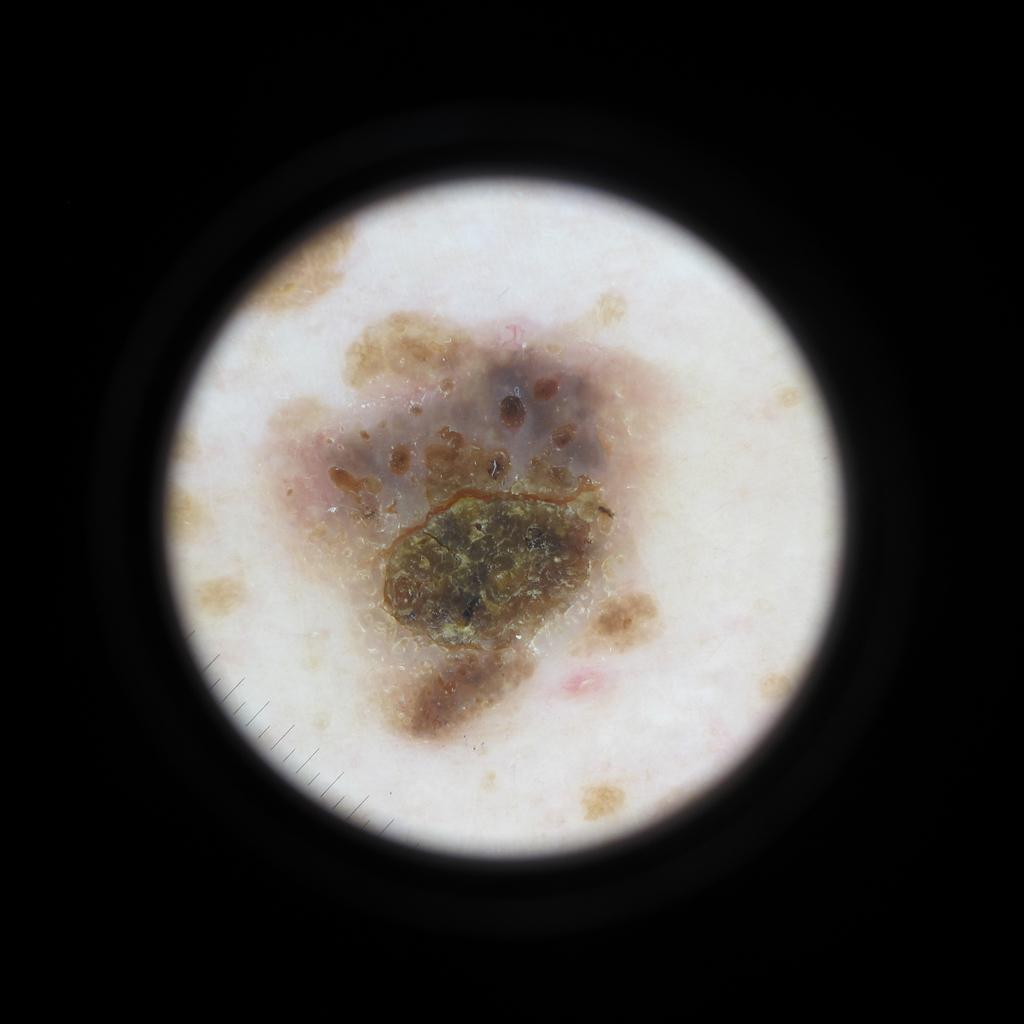

Case: 37